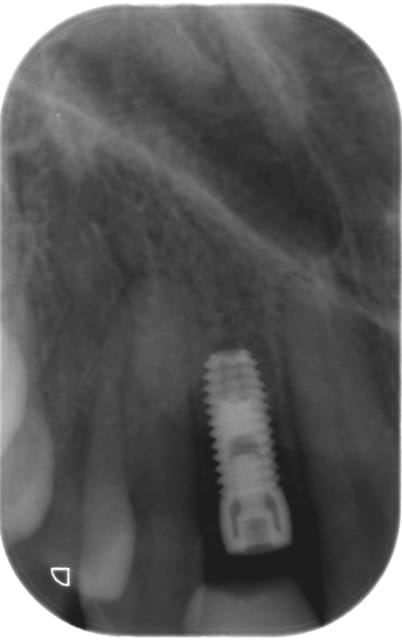

implant posé en 12 (agénésie) il y a 4 mois, le cbct montrait environ 4,4 mm en VP j'ai donc posé un 3,3/10 Zimmer (pas en TSV, qui commence à 3,7 de diamètre mais en SV)

ci joint les radio : le jour de la pose : os autour de l'implant, et cbct préop et .... radio et cbct à 4 mois...

Sur la rétro on suspecte une résorption proximale. C'est pt être juste à cause de la radio.